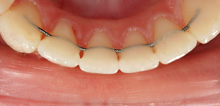

Mini-Brackets

Die im Vergleich zu Standardbrackets geringere Größe der Minibrackets sieht im Mund nicht nur besser aus, sondern erhöht auch den Tragekomfort der festen Spange, Irritationen der Schleimhäute durch Ecken und Kanten sind seltener.

Reibungsarme SL-Brackets

Dies sind Brackets, bei denen auf Grund ihrer besonderen Konstruktion die Behandlungsbögen nicht mittels Ligaturen befestigt werden müssen. Wegen der dadurch erheblich verringerten Reibungskräfte bewegen sich die Zähne schneller und mit geringeren Kräften. Die Zahnbewegungen sind somit auch weniger schmerzhaft.